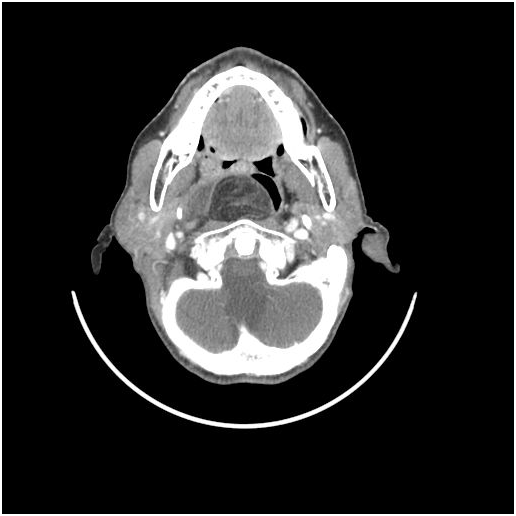

Fibrolipomas have been defined as a subtype of lipomas that are benign soft tissue tumors according to the WHO classification [1]. They differ from classic lipomas with being connective tissue bands involved among the mature adipose tissues [2]. Fibrolipomas have been described in the esophagus, pharynx, colon, trachea and larynx [3,4]. Rarely may they be seen in the oral cavity and in the maxillofacial area. In the oral cavity, fibrolipomas are most commonly found in the buccal region followed by tongue, lower lip and the parotid region; respectively [5,6]. Retropharyngeal space is an area extending from the skull base to the mediastinum, located between the middle and deep layers of the cervical fascia. It contains a small amount of fatty tissue and chains of lymph nodes especially at the suprahyoid level [7]. Lymph nodes and lymphatic channels are the main components of this space [8,9]. Tumors of the retropharyngeal region are extremely rare. The most commonly seen mass is in a form of inflammatory or tumorous lymph node enlargement [7]. Reported cases of lipomas in this region are less than 40 in the literature [10]. Whereas retropharyngeal fibrolipoma was reported by Huang in a 17-year-old male patient in 2008 and by Ganakalyan et al. [12] in a 2-year-old pediatric patient in 2008 [11] (Figures 1-3).

Figure 1-3: Axial ct scan showing fat density mass in retropharyngeal space.